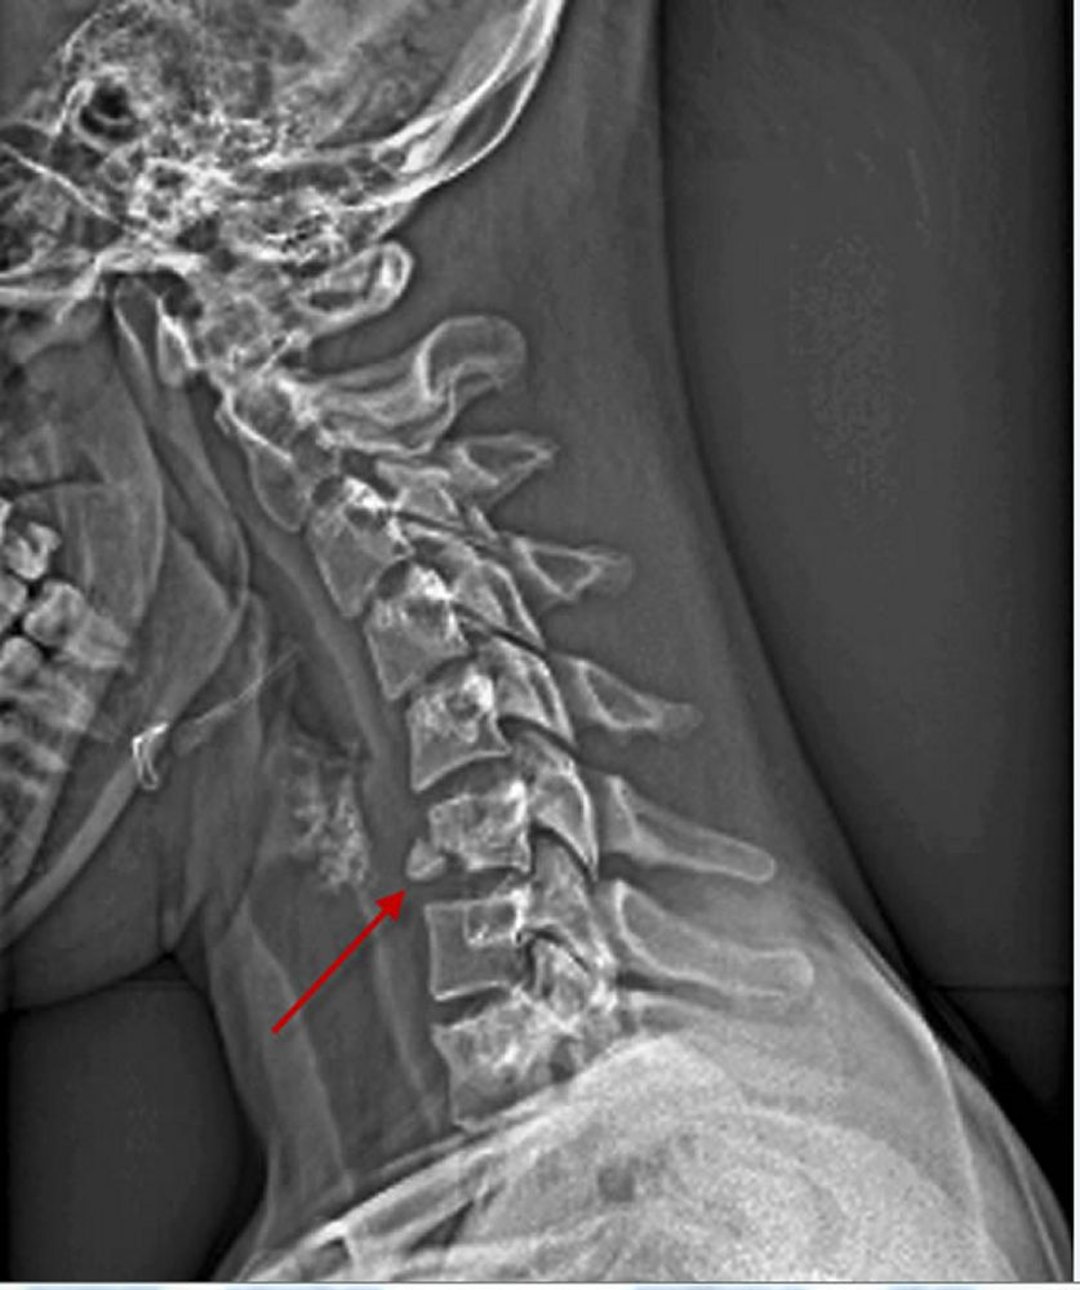

Vértebra cervical fracturada

Fractura del cuerpo vertebral cervical

Si se identifica una fractura, una subluxación o una lesión ligamentosa de la columna cervical, generalmente se justifica un estudio vascular (típicamente, angiografía por TC) para descartar lesiones concomitantes en la arteria carótida o la arteria vertebral.